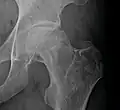

Head of the femur showing a flap of cartilage due to avascular necrosis (osteochondritis dissecans). Specimen removed during total hip replacement surgery.